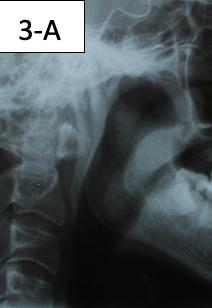

Clinical appraisal of the Airway revealed a patent airway; lower airway -15/18 mm, oropharynx - Mallampati II -III, nasopharynxvery patent (Figure 3-A, B, C).

FIG.3A: Pre-treatment, lower airway

FIG. 3B: Pre-treatment, oropharynx

FIG. 3C: Pre-treatment nasopharynx

The patient had the following: migraine headaches, sore teeth upon awakening, buzzing in his ears, teeth clenching and grinding, joints locking when opened wide, popping, and clicking, pain and problems sleeping soundly. He had normal range of motion, deviation to the right on opening, clicking, The patient also had a sensitivity to palpation on the right TMJ, Posterior neck left, Trapezius left and Anterior digastric bilaterally. The transcranial TMJ radiogram reveals posteriorly displaced condyles and limited maximum opening on the right side (Figure 5-A).

Lateral Cephalometric radiogram and tracing revealed robust lower airway (18.0/15mm), CVMS 6, maxilla and mandible are prognathic (SNA - 93° and SNB - 84°), Class II skeletal (ANB –9.0 mm, Witts – 9.0 mm). The patient was hyperdivergent (NS/ GoM – 30°, ALFH - 83 mm!!), protrusive maxillary incisors (U1/ SN – 117.0°), mandibular incisors were within the norm (L1/GoM 95.0°) and Harvold Δ was 30 mm. The soft tissue profile (lips) was convex (Figure 5-C, D).